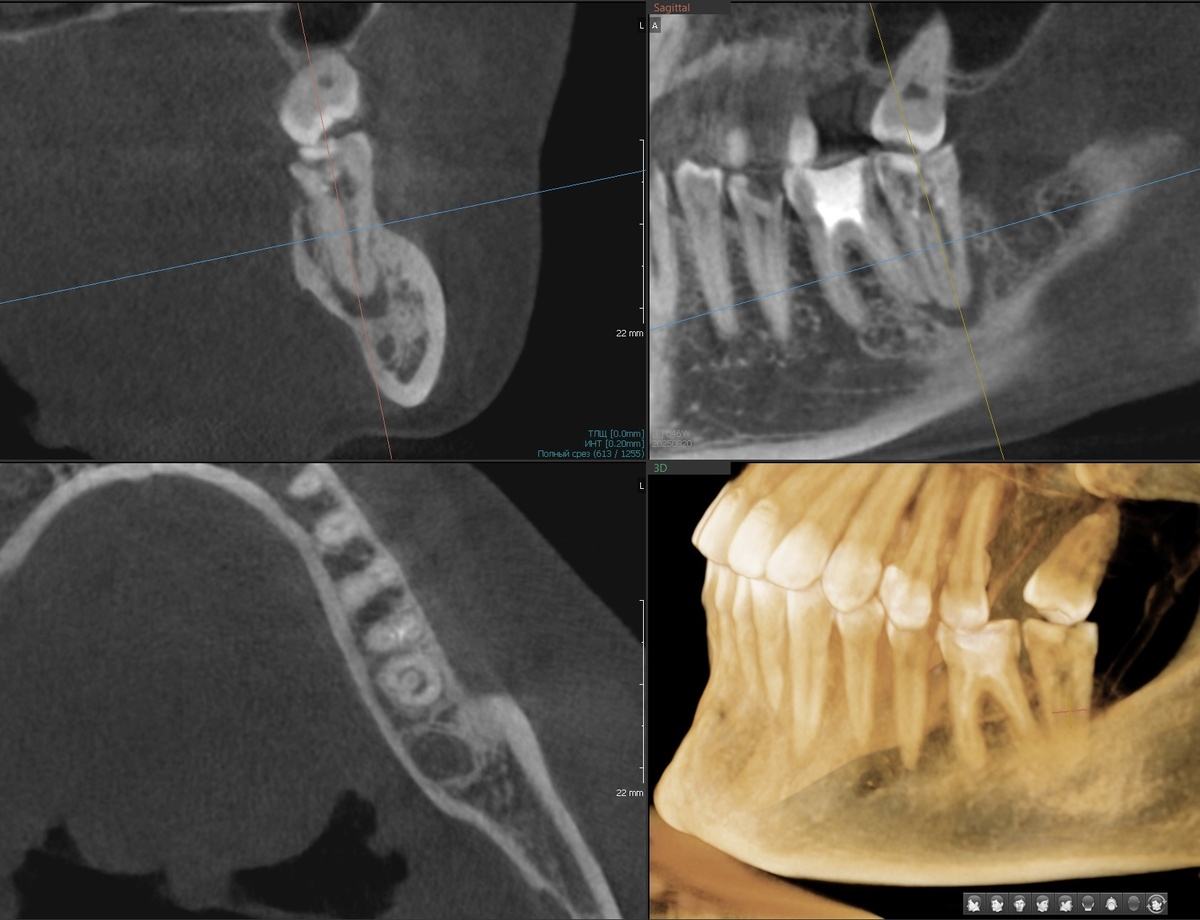

Сюрприз на рентгенограмме обнаружился случайно- на нижней семёрке слева (зуб 3.7) весомый очаг деструкции, у верхушки корня. Периодонтит!

Зуб 3.7 - каналы "пустые", периодонтит (тёмный очаг около верхушки корня)

C-shaped (С-образная конфигурация) - это анатомическая аномалия корневых каналов, встречающаяся в 10-45% нижних вторых моляров у азиатского населения и в 2-8% у европейского.

Вместо отдельных круглых каналов - один канал в форме буквы С. На снимке КТ прекрасно видно, о чём я говорю.

На КТ наблюдается классическая картина - тёмное пятно у верхушки корня, разрежение костной ткани. Хроническое воспаление без боли, никак себя не проявляющее. Это самое коварное - организм адаптировался, воспаление инкапсулировалось, но оно есть. И в любой (обычно, в самый неподходящий) момент при снижении иммунитета может рвануть острым воспалением.